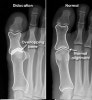

X-ray : 발가락 관절의 탈구(MTPJ Dislocation)

X-ray 촬영을 실시합니다.